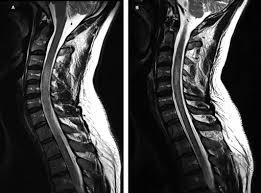

Early Radiological Features Of Severe Longitudinally Extensive Transverse Myelitis Over Time Journal Of The Neurological Sciences

Early Radiological Features Of Severe Longitudinally Extensive Transverse Myelitis Over Time Journal Of The Neurological Sciences from els-jbs-prod-cdn.jbs.elsevierhealth.com

The early prediction of recurrence after an initial event of transverse myelitis helps to guide preventive treatment and optimize outcomes.